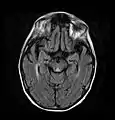

صورة محورية عن طريق الرنين المغناطيسي FLAIR تظهر إشارة في الوسط المهادي ظهري ، وهو شيء شائع في الاعتلال الدماغي المرتبط بمتلازمة فيرنيك. كان هذا المريض تقريبا في حالة غيبوبة عندما بدأ تمديده بالثيامين وريدياً ، استجاب بشكل جيد لكنه ترك بعض العجز المرتبط بمتلازمة كورساكوف.